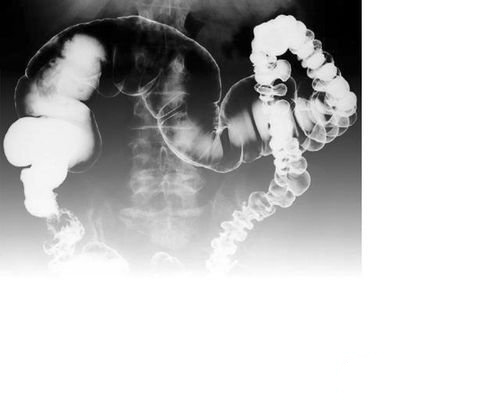

结肠炎|直肠炎|肠息肉

溃疡性结肠炎|克罗恩病

肠易激综合征|十二指肠炎